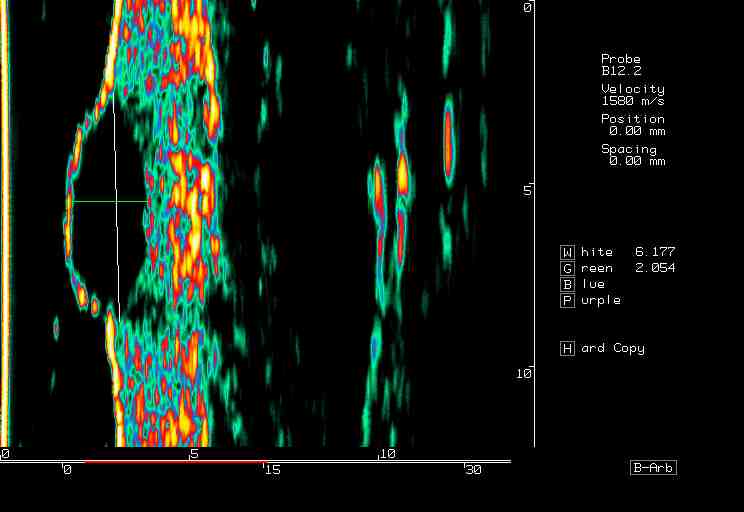

| Tumors |  BCC on the ear |

BCC, various sites |

BCC pre PDT |

BCC post PDT |